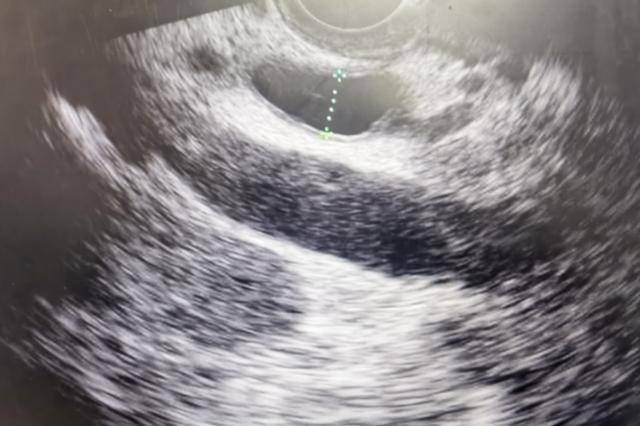

胰腺位于腹腔深处,位置很“隐蔽”,前有胃、后有脊柱,做B超不容易看清,很多早期小病灶根本“照不到”。

完善影像检查:普通腹部B超容易漏掉早期病变,医生通常会根据情况选择增强CT、MRI或胰腺专门超声、内镜超声等,更有助于发现小病灶。